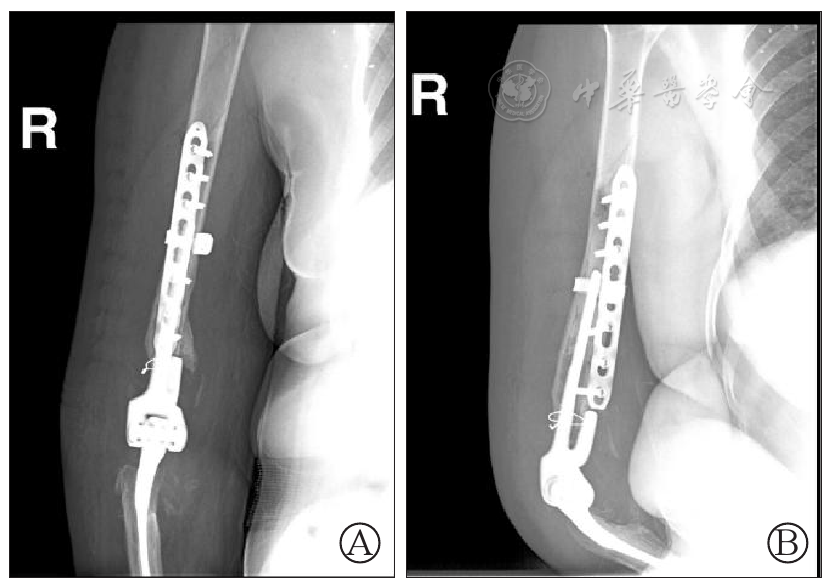

图5 右肘关节假体周围骨折术后正(图A)、侧(图B)位片:右肱骨骨折断端对位对线尚可,内固定稳定,周围软组织内可见小游离骨折碎片,右侧人工肘关节位置良好